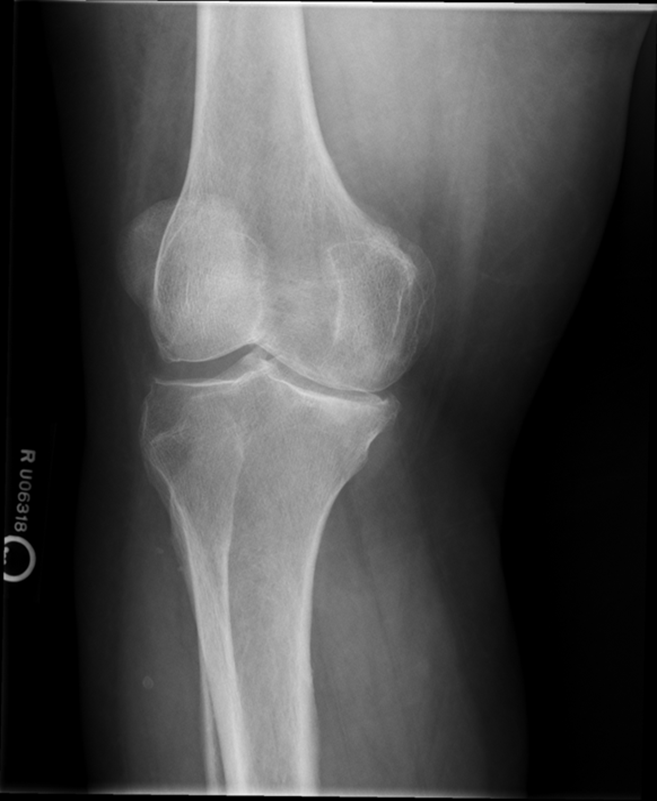

Osteochondroma

(Exostosis)

Benign projection of bone with a cartilaginous cap

Cause: idiopathic, hereditary

Complications: may turn malignant, pain, fracture of stalk

Radiographic Appearance: long axis of bone growth runs parallel to the parent bone and points away from nearest joint

Technical: No manual exposure factor change

Prognosis: Good, surgery only needed when there are mechanical

impingements